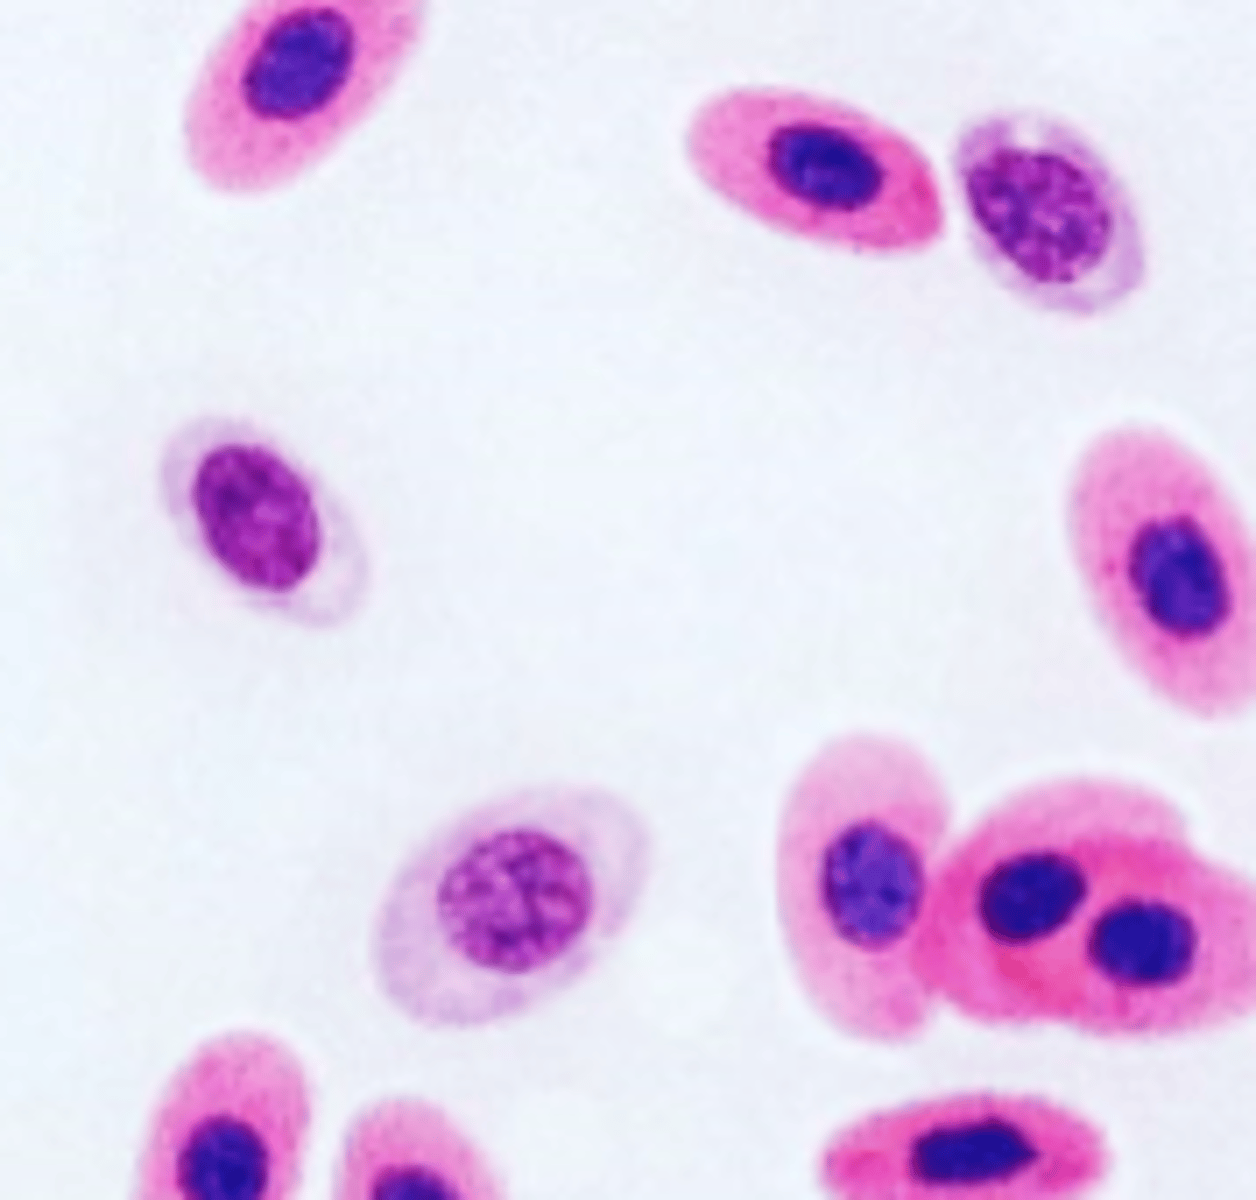

heterophils (neutrophils of exotics)

exotic

large size

nucleus bilobed to round

colorless cytoplasm, filled with orange to brick-red granules (might appear fused)

heterophil

exotic

fused heterophil

exotic

toxic heterophil

exotic